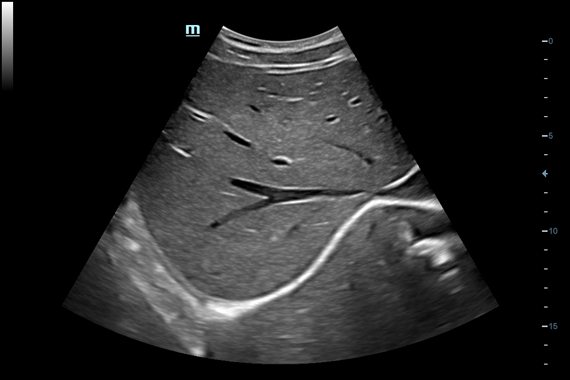

Система ультразвукового исследования Mindray DC-60 EXP X-INSIGHT является новейшей разработкой для проведения комплексных обследований на высшем уровне. Она обеспечивает решение самых сложных задач в таких областях, как кардиология, акушерство и гинекология, сосудистые заболевания, педиатрия и многие другие.

DC-60 EXP X-INSIGHT - это современный стационарный УЗИ-аппарат с функцией сенсорного управления и очищенной гармонической визуализацией, обеспечивающей лучшее контрастное разрешение и технологию 4D-визуализации. Он оснащен 21,5-дюймовым монитором, который может поворачиваться на 180 градусов, что удовлетворяет потребности врачей в качественной ультразвуковой диагностике.

• Набор услуг Shared Service Package, который включает предустановленные параметры, аннотации, маркеры, программы измерений для различных исследований, включая абдоминальные, акушерские, гинекологические, кардиологические, ангиологические, исследования малых органов, урологические, педиатрические и неотложные случаи.

Одним из ключевых преимуществ DC-60 EXP X-INSIGHT является технология формирования УЗ-луча. Она дополняет основной луч параллельно эхо-сигналами, что приводит к получению более мощного сигнала и изображений высокого качества с помощью систем iLive, iPage, Smart OB, Smart NT.